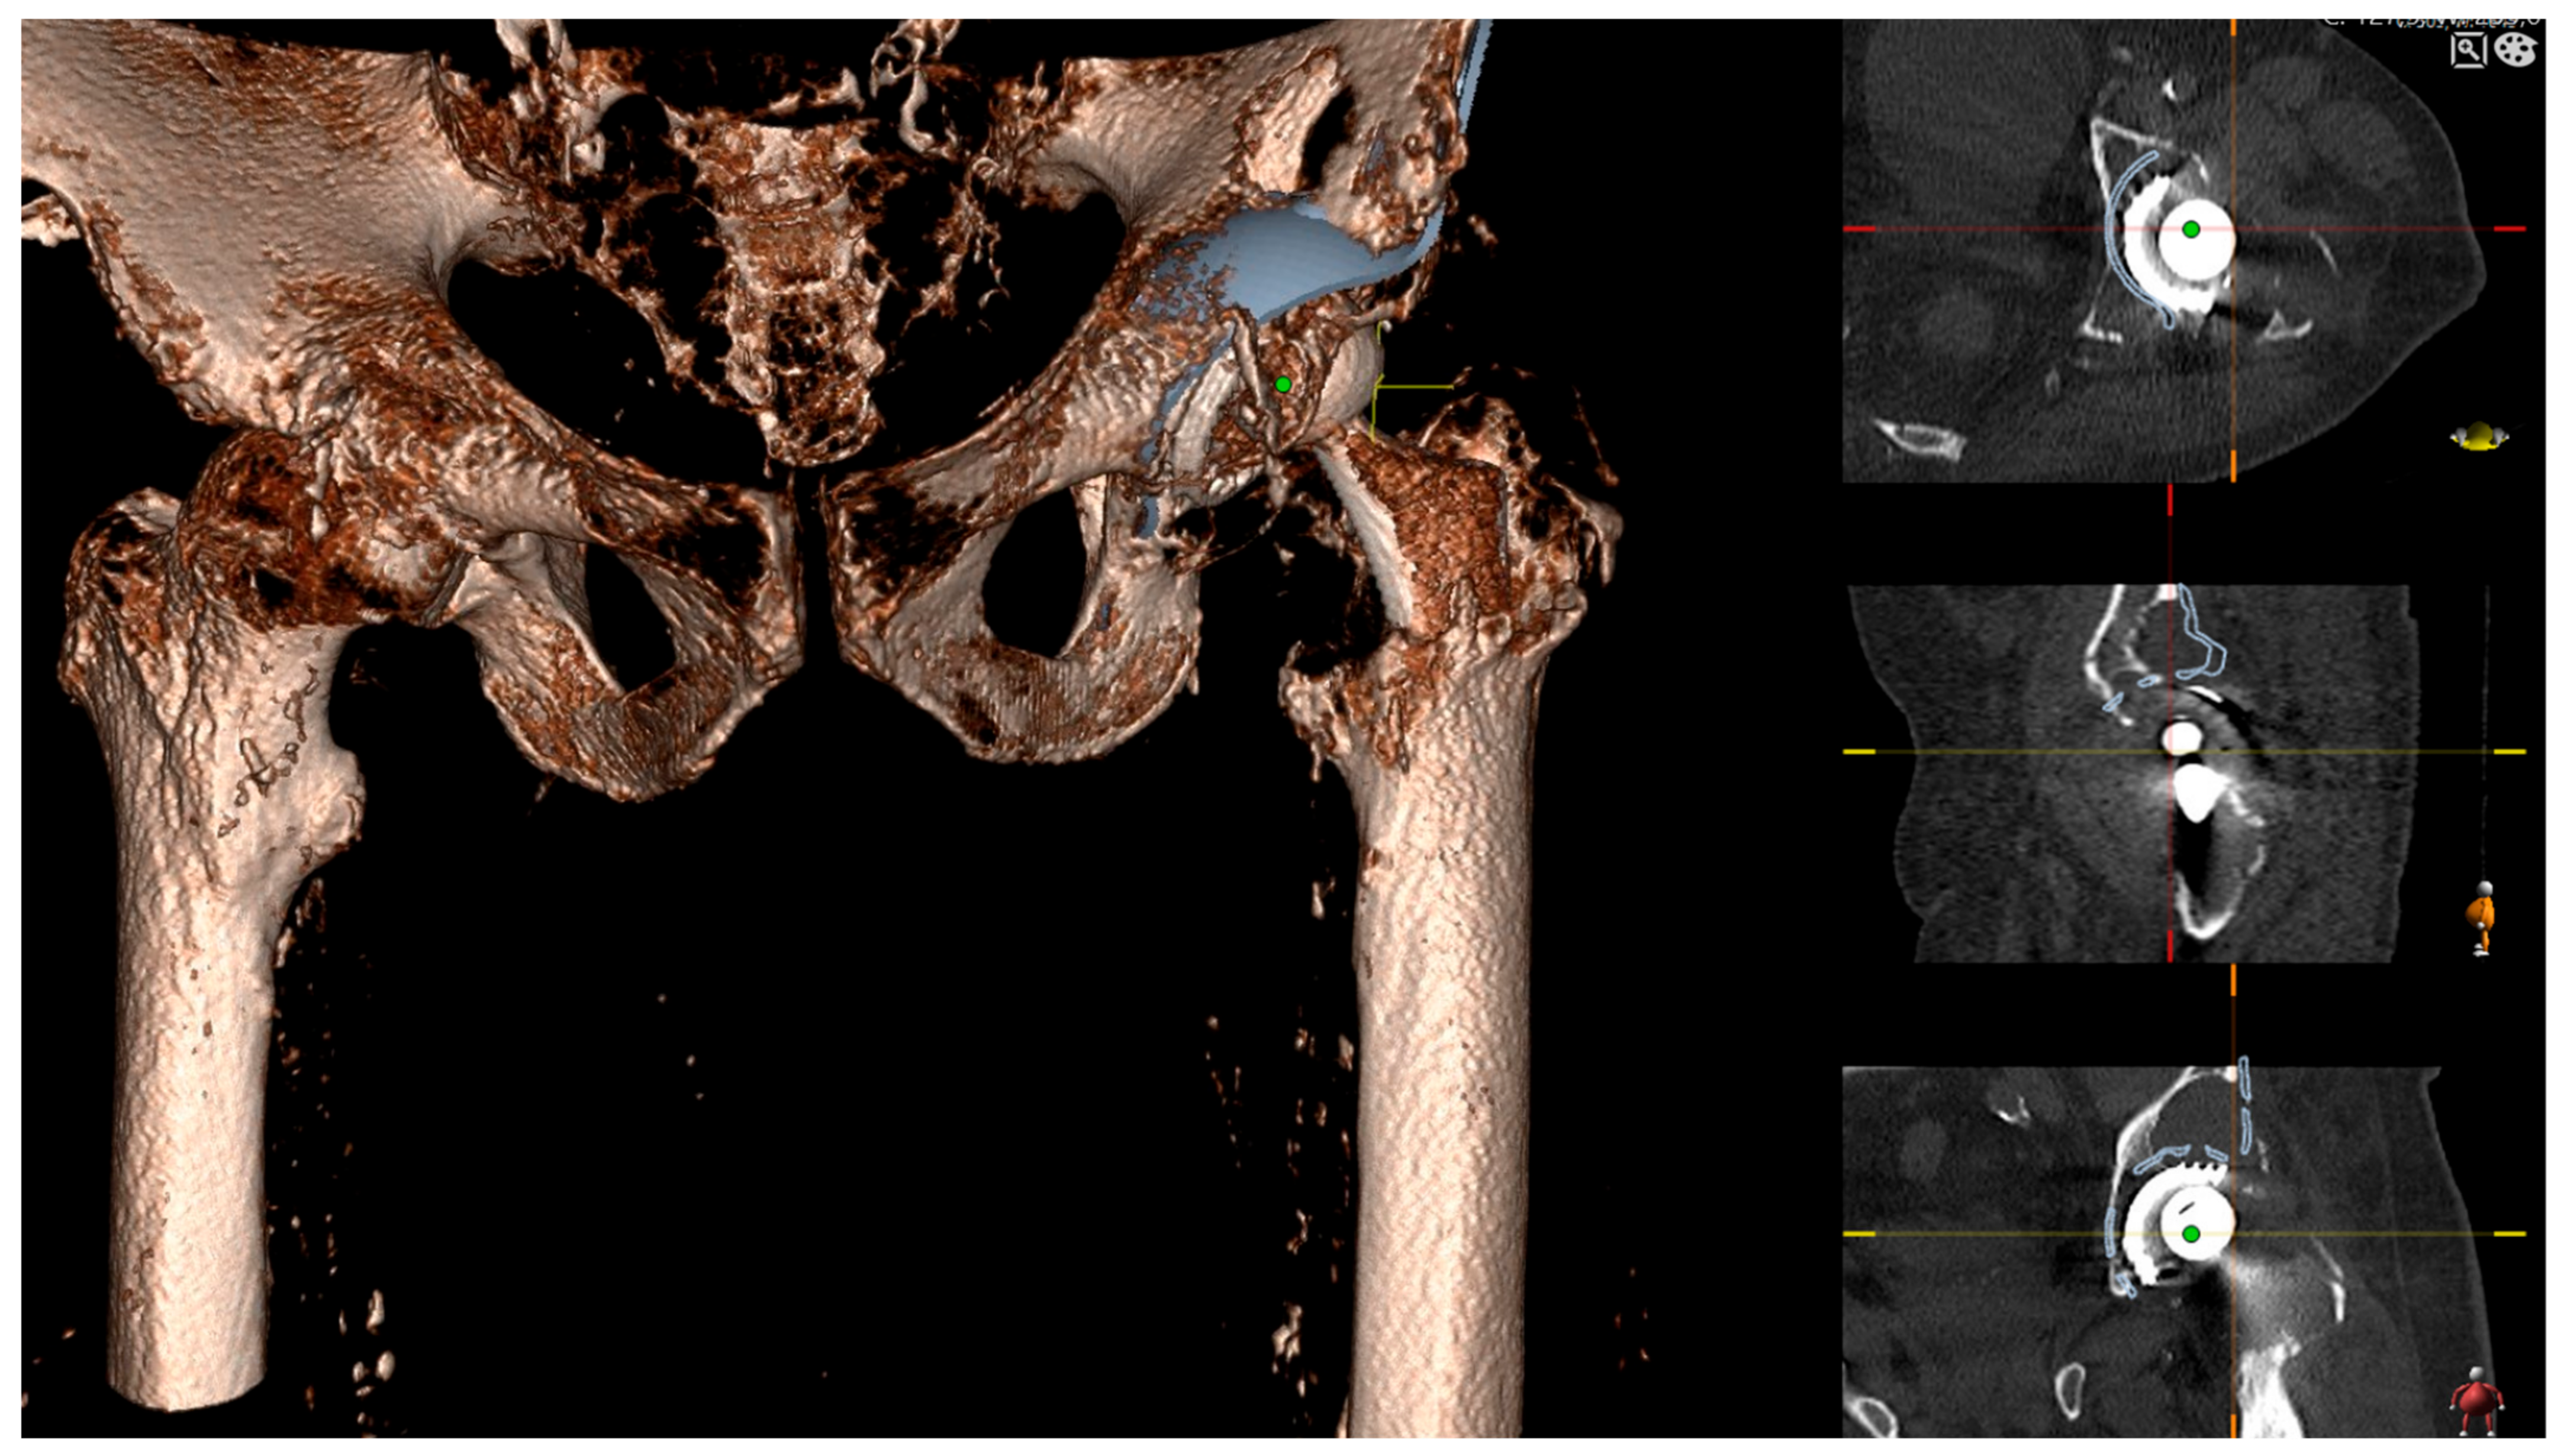

Figure 5. Planning of the screw fixation of the Burch Schneider reinforcement cage. The optimal screw positioning was preoperatively planned by 3D CT imaging.